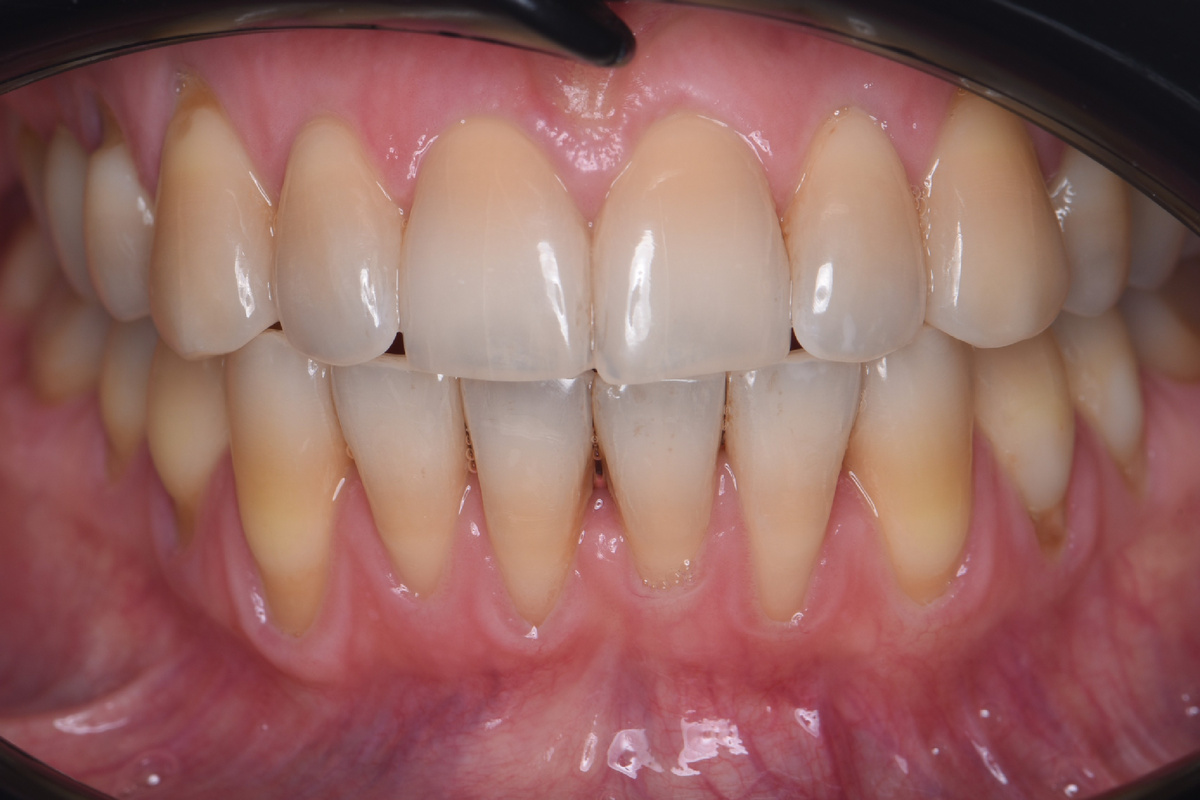

Рецессия десны — это оголение корня зуба, когда десна опускается и зуб визуально становится длиннее. Люди чаще всего спрашивают: почему уходит десна, почему оголился корень, и что делать, когда обнажается десна. Этиология рецессии мультифакторная. Это означает, что причины встречаются либо в совокупности, либо один фактор действует настолько сильно, что запускает процесс сам по себе. Важно разделять предрасполагающие факторы и триггерные, то есть те, что создают условия, и те, что запускают сам механизм. Предрасполагающие факторы 1. Мальпозиция зубов (аномальное положение) Когда зуб стоит неправильно — выступает, ротирован, наклонён — риск рецессии увеличивается по нескольким причинам. Во-первых, уменьшается толщина вестибулярной альвеолярной кости. При выраженной мальпозиции кость может становиться настолько тонкой, что появляются фенестрации и дигисценции. Фенестрация — это ограниченный участок корня, который не покрыт костью. На этом уровне корень покрывает только десна. Диг

Рецессия десны — это оголение корня зуба, когда десна опускается и зуб визуально становится длиннее. Люди чаще всего спрашивают: почему уходит десна, почему оголился корень, и что делать, когда обнажается десна.